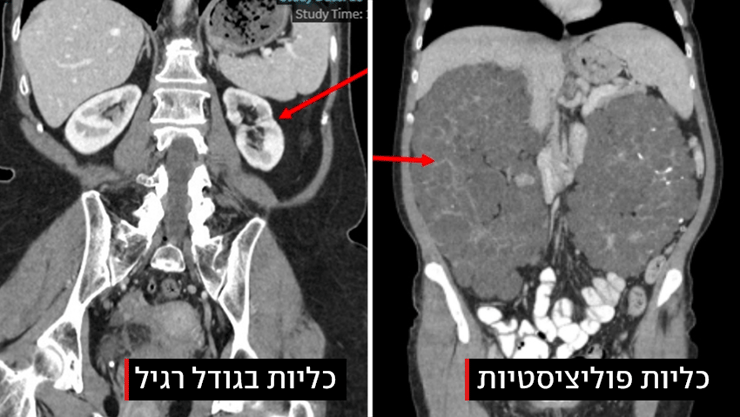

במקביל, הכליות שכבר חדלו לתפקד המשיכו לגדול, ובשלוש השנים האחרונות הגיעו לממדים חריגים ומילאו את מרבית חלל הבטן. ד"ר רז מציינת כי משקלן הכולל הגיע ליותר מחמישה ק"ג, בעוד משקל כליה בריאה נע בין 120 ל-170 גרם בלבד. אחת הכליות גדולה פי 15 מכליה בריאה. אורכן של הכליות הגיע לכ-35 ס"מ, לעומת כ-10 ס"מ של כליות בריאות. "זה מקרה נדיר במיוחד", אומרת ד"ר רז. "אחת הכליות נמנית עם הגדולות שתועדו בספרות המקצועית בשנים האחרונות. גודל ומשקל הכליות דומים לאלה של שני עוברים".

הכליות של אוליאנה שבלה מימין, לעומת כליות בגודל תקין משמאל